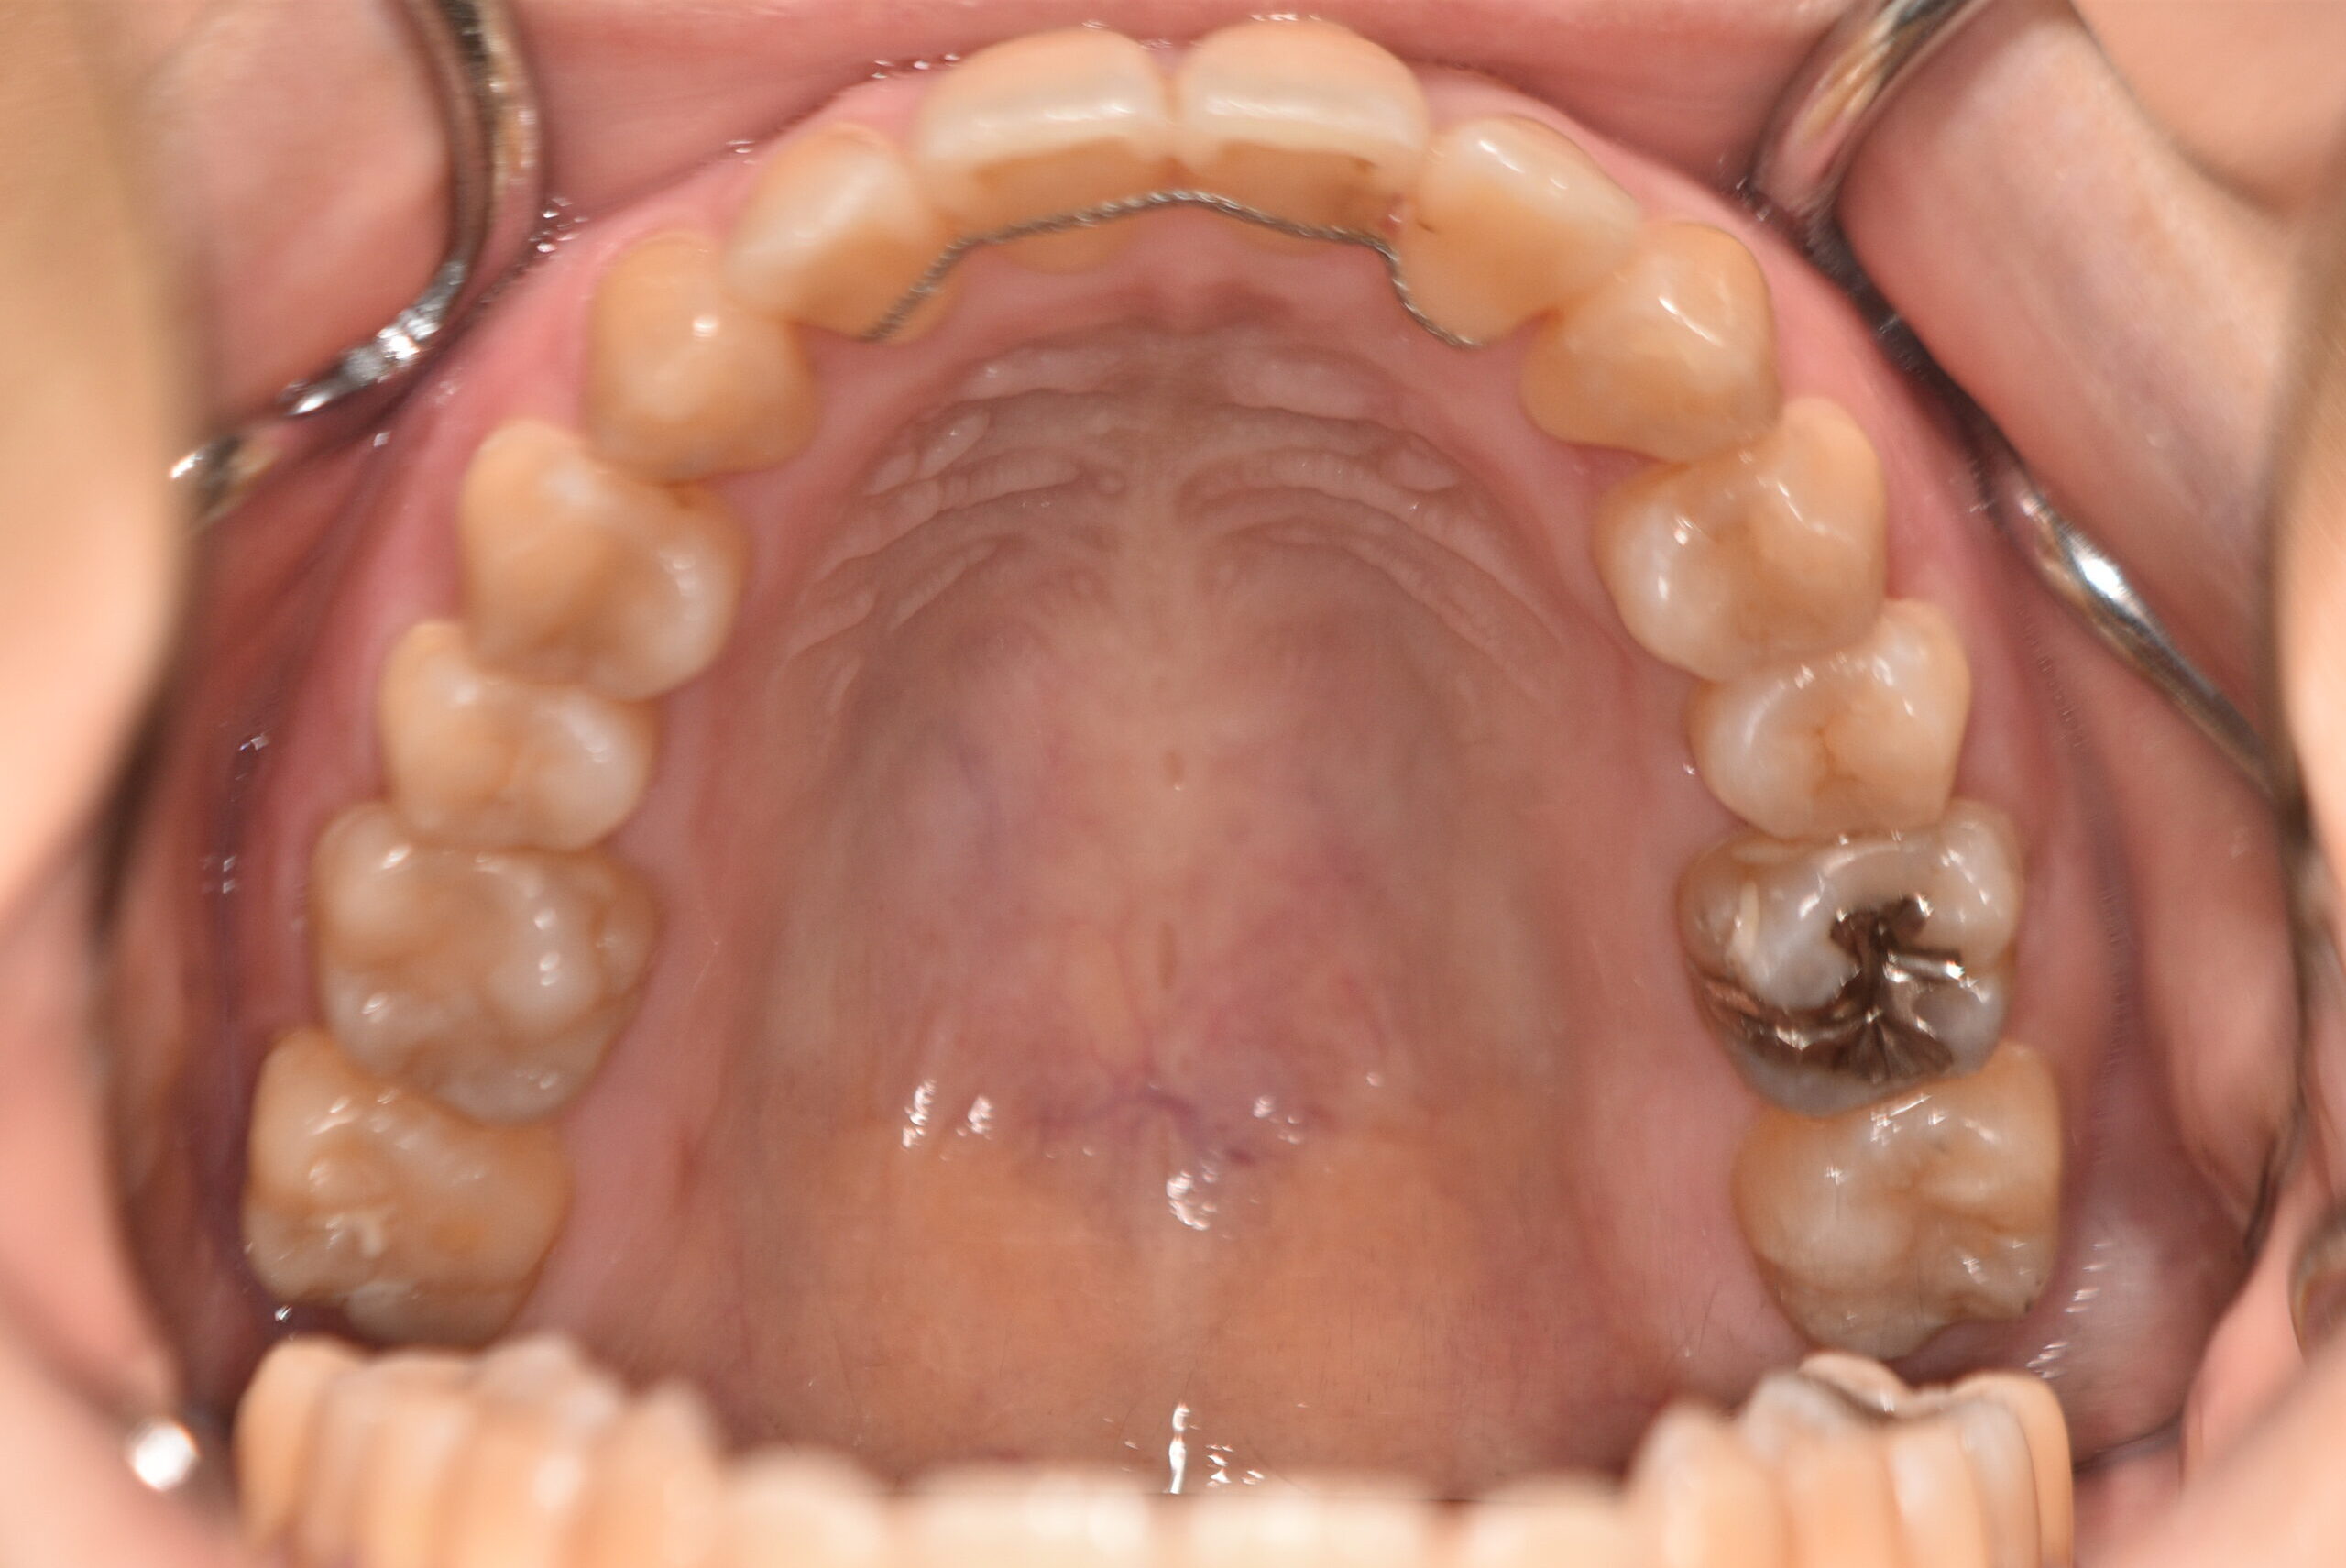

| 治療内容の詳細 | 初診時31歳の女性で、前歯が奥側にあることを気にされ来院されました。 検査の結果、上下顎叢生を伴うアングルⅠ級不正咬合と診断しました。 治療としては、上顎臼歯部の遠心移動を行い、歯を配列するためのスペースを確保し、非抜歯の上、セルフライゲーションブラケット装置(デーモンシステム)で歯の配列と咬合関係の改善をを行いました。 治療期間は、2年7ヶ月でした。 |